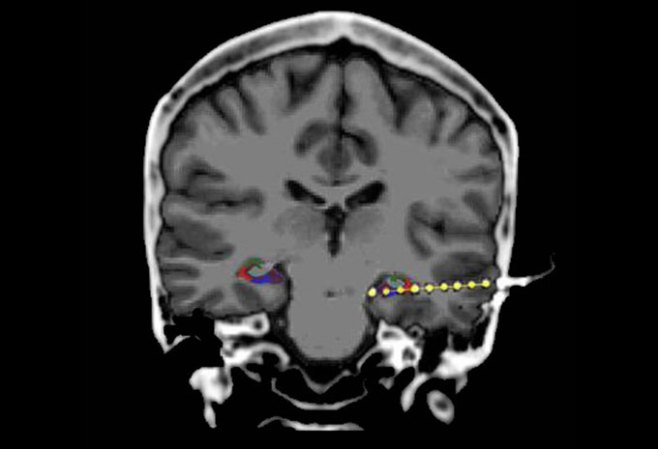

ALTOGETHER NOW Fast ripples of activity appear in the hippocampus, a memory center in the brain, right before a person describes a previously seen image, a study finds.

Movus/iStock/Getty Images Plus